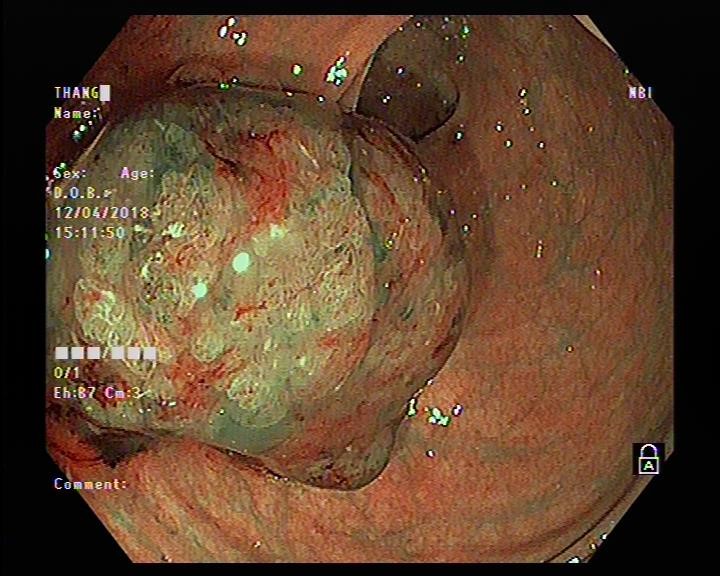

UNG THƯ ĐẠI TRỰC TRÀNG VÀ KỸ THUẬT NỘI SOI CHẨN ĐOÁN SỚM

20/06/2022 (GMT+7)

Ung thư đại - trực tràng  (Colon Cancer) là một trong những bệnh ung thư phổ biến trên thế giới. Theo thống kê  năm 2012 của Globocan, ung thư đại trực tràng đứng thứ 3 về tỷ lệ mắc (10%) và thứ 4 về tỷ lệ tử vong (8,5%) do ung thư. Ở Mỹ, ung thư đại trực tràng đứng hàng thứ tư về tỷ lệ mắc và thứ 2 về tỷ lệ tử vong. Tại Việt Nam, ung thư đại trực tràng nằm trong số 10 bệnh ung thư thường gặp, có xu hướng gia tăng. Tỷ lệ mắc chuẩn theo tuổi là 10,1/100.000 dân, đứng hàng thứ sáu trong các bệnh ung thư của cả 2 giới.